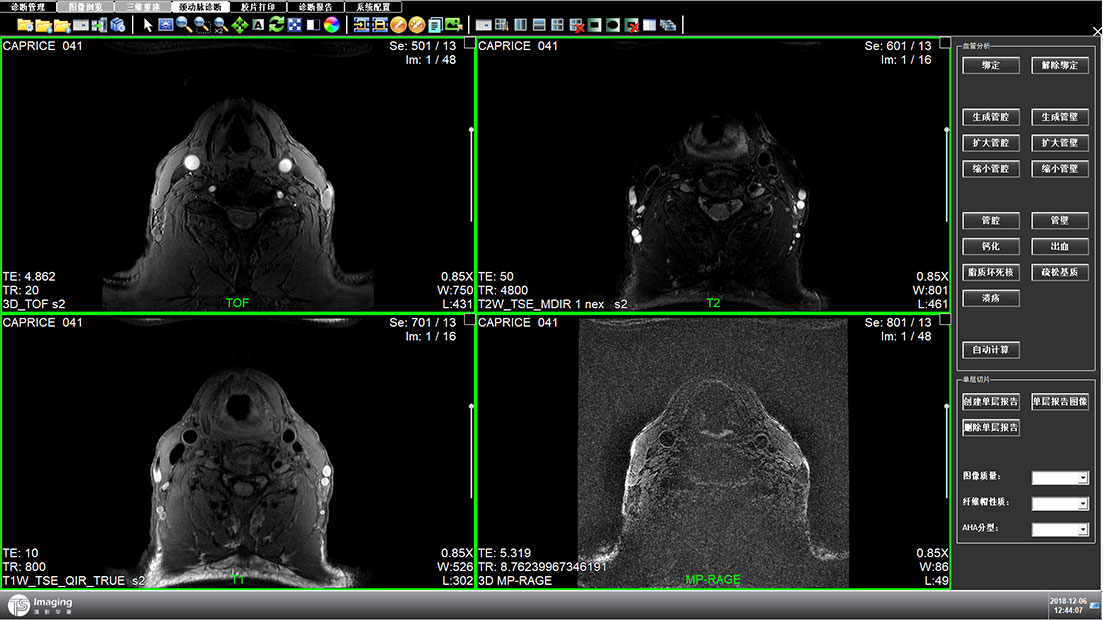

診斷管理頁面

診斷管理頁面相對其他頁來說交互關(guān)系比較復(fù)雜,表單里面還套了一個(gè)子表,為了更好的區(qū)分兩者,tab的形式、底色和字體大小等等做了明顯的區(qū)分。這部份也是在設(shè)計(jì)過程中調(diào)的較多的地方。左側(cè)是一個(gè)信息列表的展示,通過下方的按鈕也可進(jìn)行操作。下方是影像的縮略圖,點(diǎn)擊之后可放大。